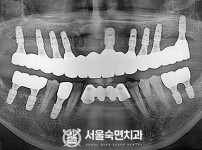

임플란트-전후사진4

임플란트-전후사진5

치과를-선택할-때-꼭-확인하세요-서울숙면치과-임플란트-전후사진